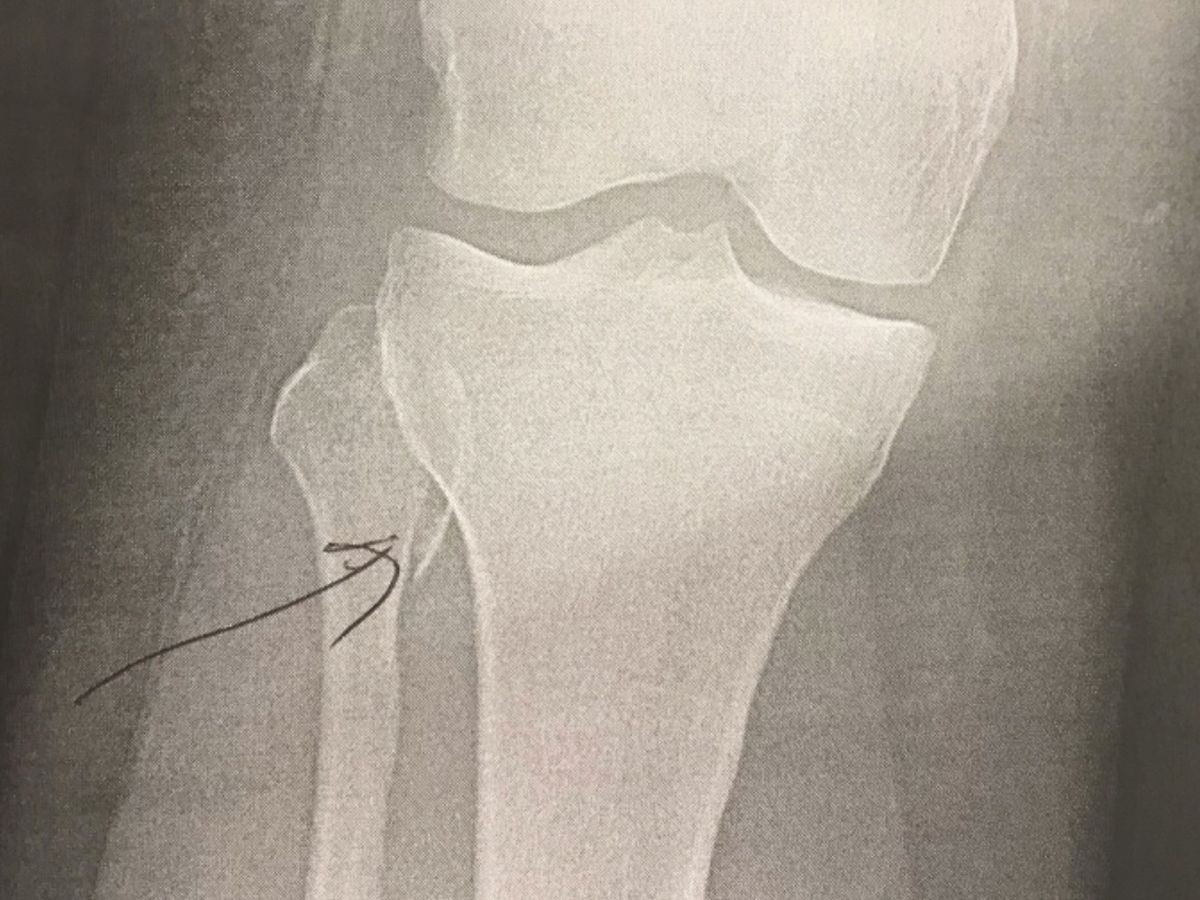

As most of you know I broke my leg 2 days into my vacation which started in November. Upon coming home, I received an MRI and a diagnosis that my ACL was completely ruptured. After 5 initial weeks of therapy, it was decided that I needed to go into surgery to have my ACL replaced.